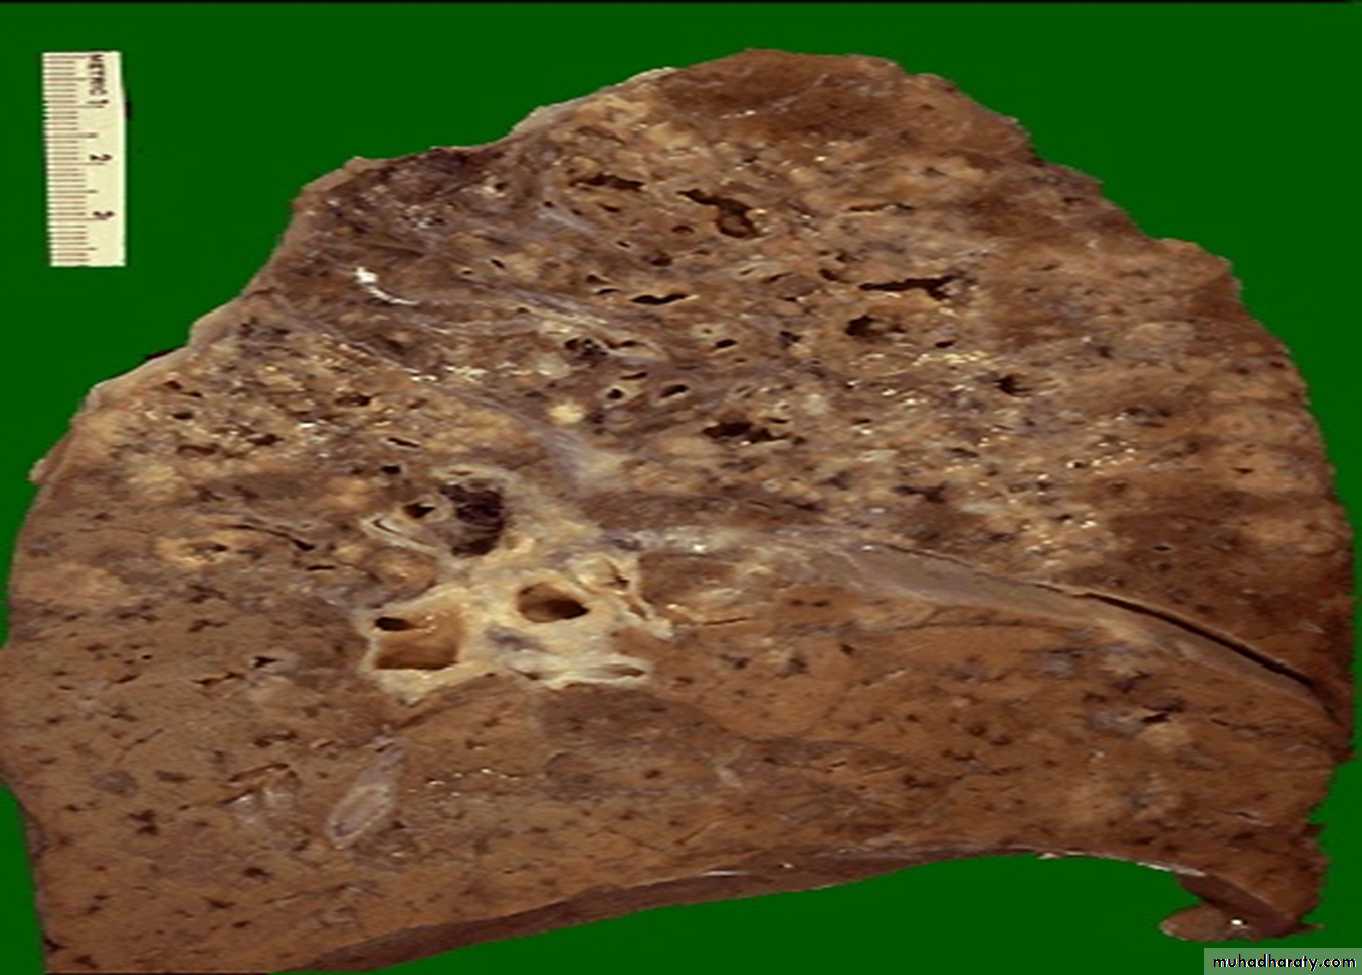

* Macroscopically : occurs at the apex of the lung with marked damage in the lung parenchyma with cavity formation

* Microscopical: epithelioid granulomatous with central caseous necrosis & cavity.

Secondary T.B with Cavities